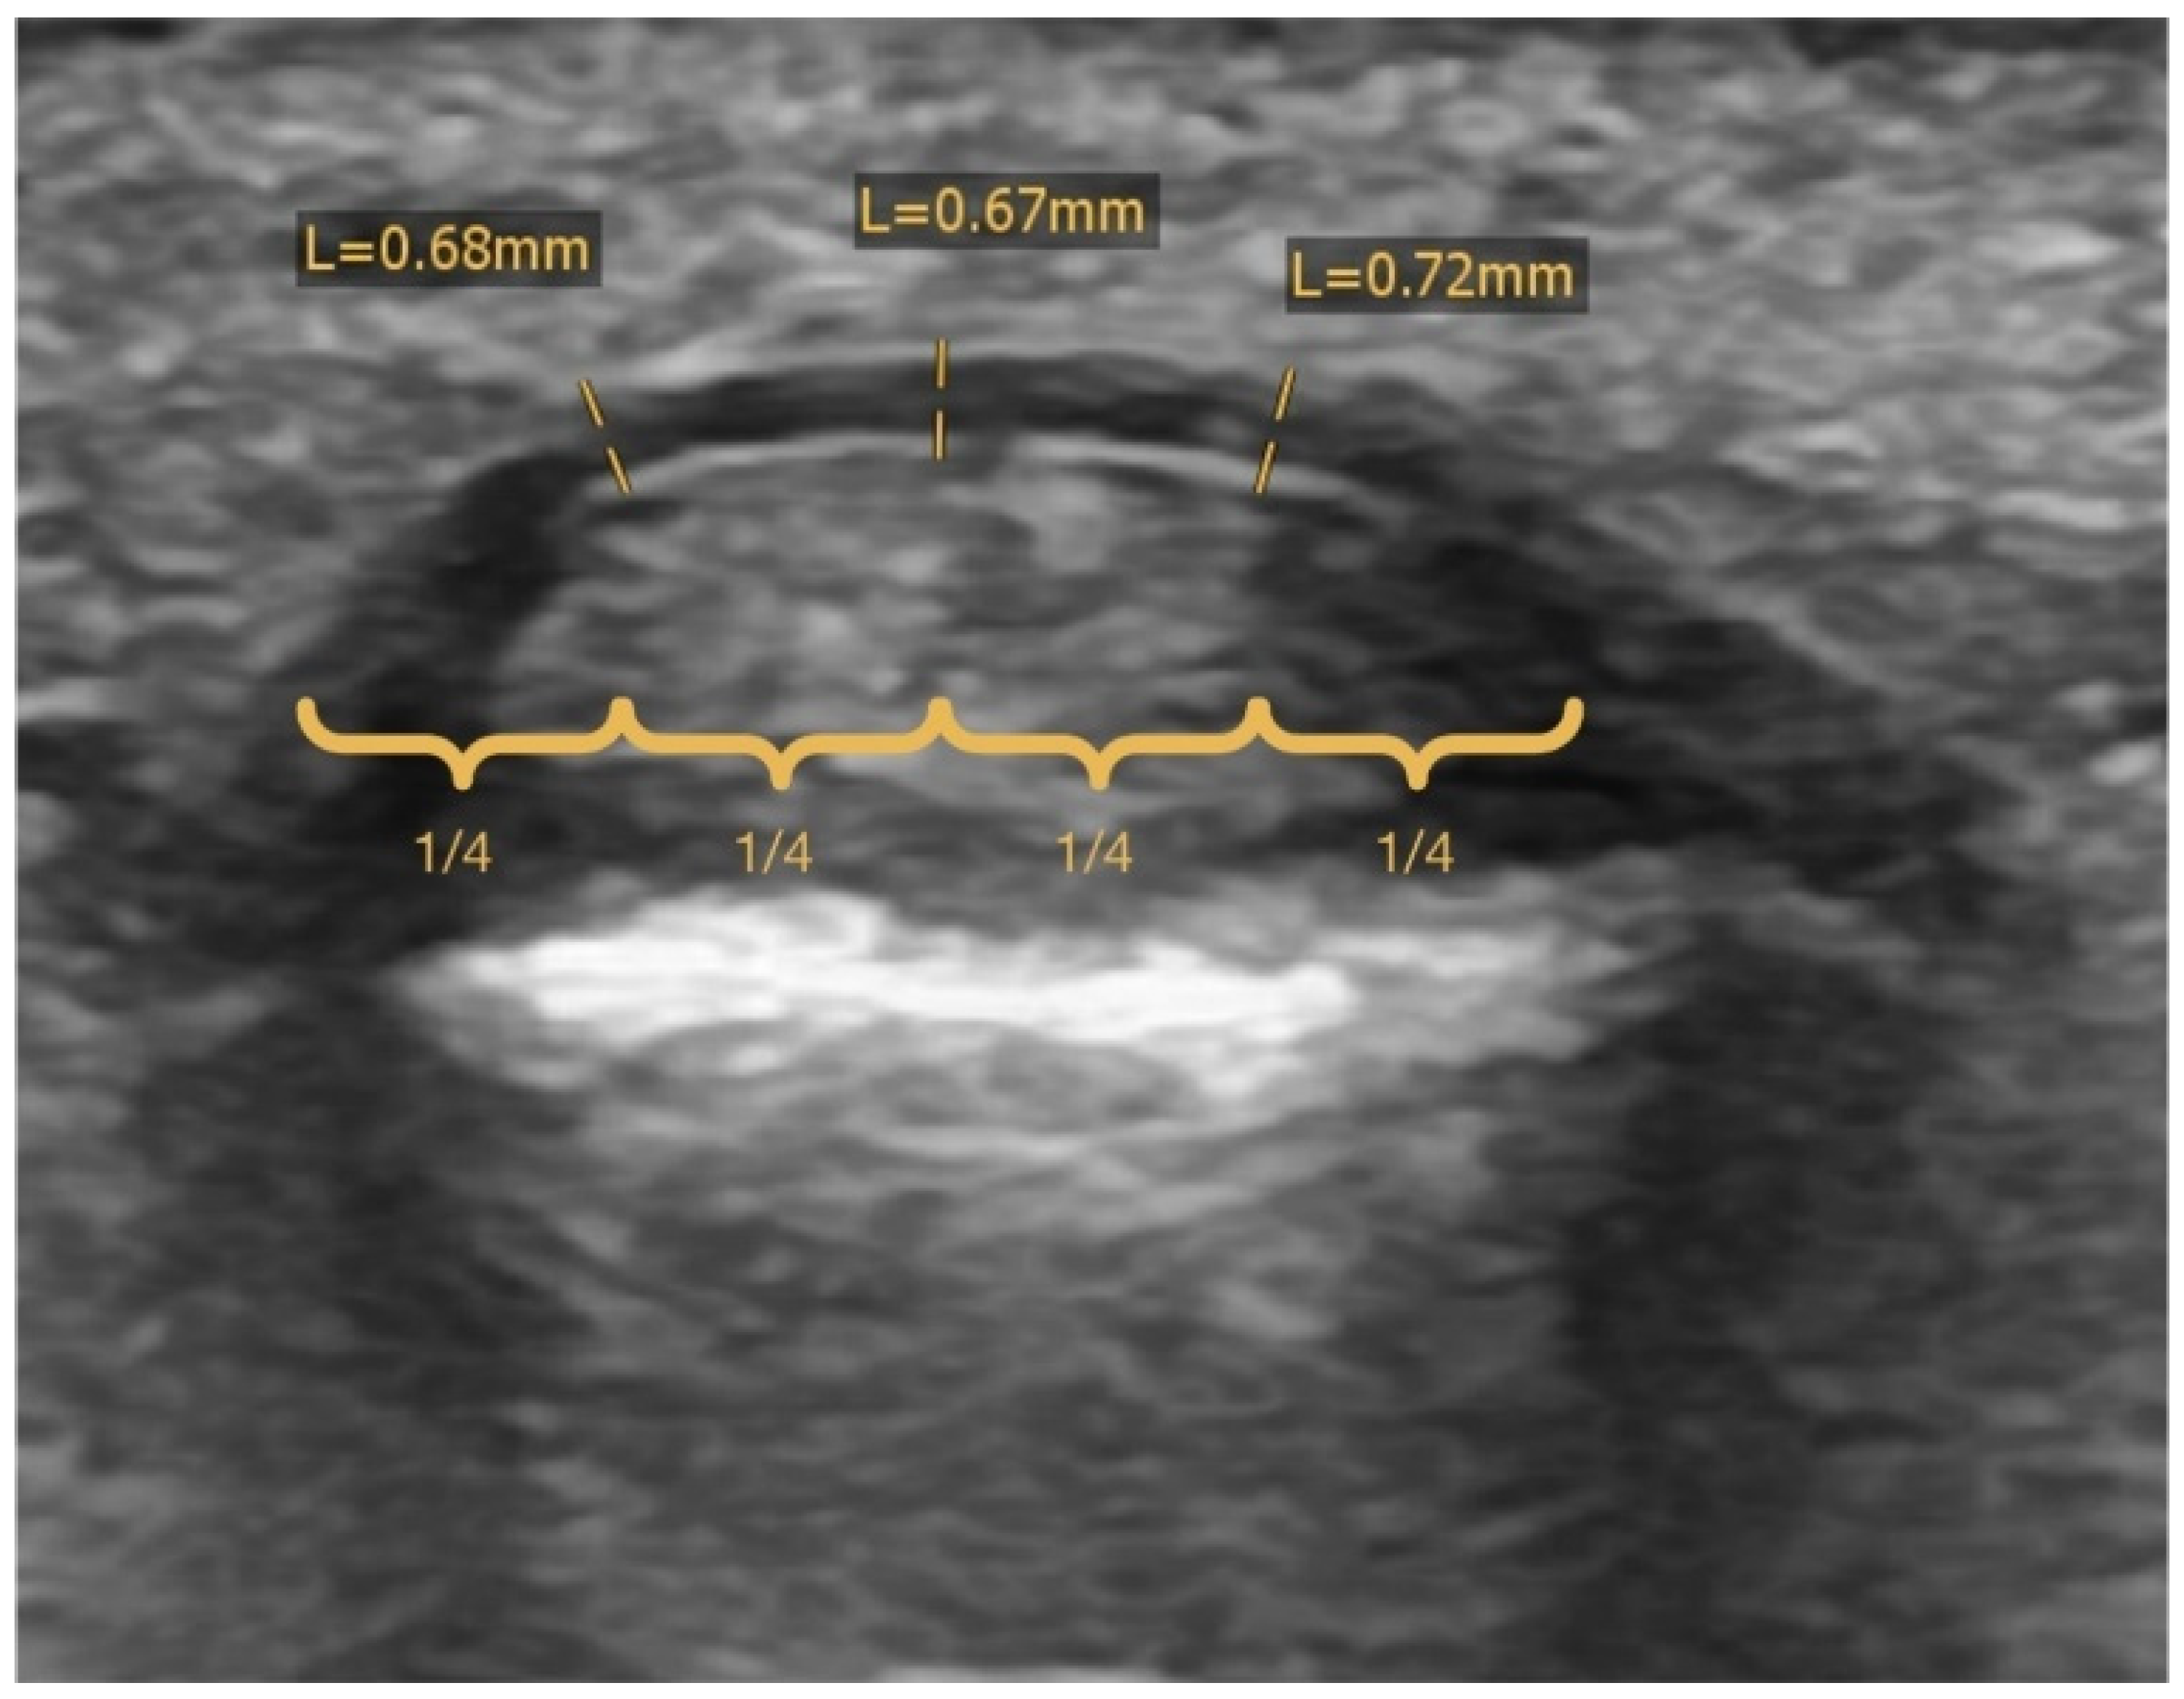

2.5. Radiographic Analysis

| average pulley thickness [cm] | 1.06 (0.95, 1.17) h | 0.97 (0.70, 1.25) d | 1.08 (0.92, 1.25) g |